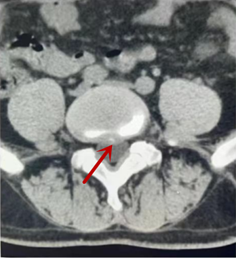

利器二:CT

CT利用X射线对人体检查部位通过电脑切成若干层扫描,然后把每层的图像都能显示出来。CT相对于X光片具有更高的密度分辨力,可直接显示X线片无法显示的病变,观察腰椎有无微小的骨折、骨质有无破坏等骨质情况、以及腰椎间盘突出、腰椎神经根、椎管、椎间小关节的情况等。同时还可以通过后处理,重建腰椎矢状位或冠状位图像,形成腰椎的3D图像,更直观地观察病变部位,对腰椎手术风险具有提示作用,对手术方式的选择具有指导意义,但是对神经、脊髓损伤程度的显示不如MRI,软组织的分辨率仍有一定限制,对椎管内病变显示欠佳,且有一定的辐射。

箭头提示椎间盘突出